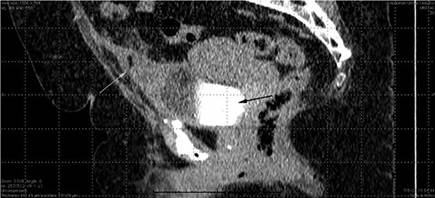

Figura 2: TAC sagital contrastada en fase de eliminación. La flecha lila muestra divertículo uracal con burbuja de aire en su interior y marcado engrosamiento de sus paredes, existe estriación de la grasa adyacente. La fecha verde muestra la vejiga con material e contraste.

FIGURA 2: